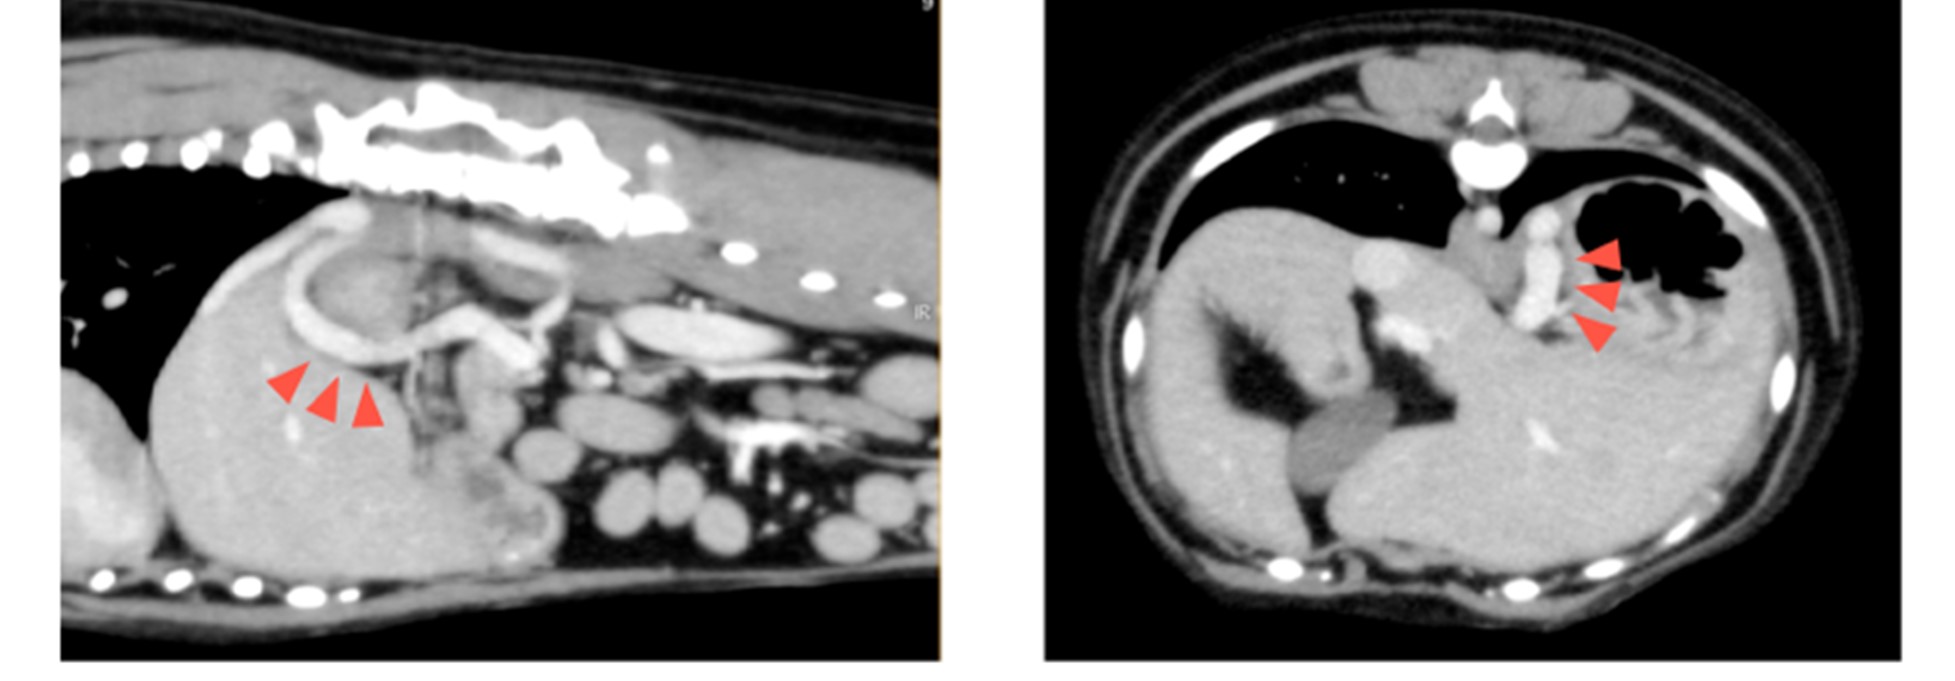

後日1回目のシャント血管結紮術を行い、3ヶ月後に再度造影CT検査を行いました。

シャント血管は残存していますが、血管径は半分程度まで細くなっていることがわかります。

肝臓は正常なサイズまで成長し、肝臓内の血管の発達も良好であることがわかりました。